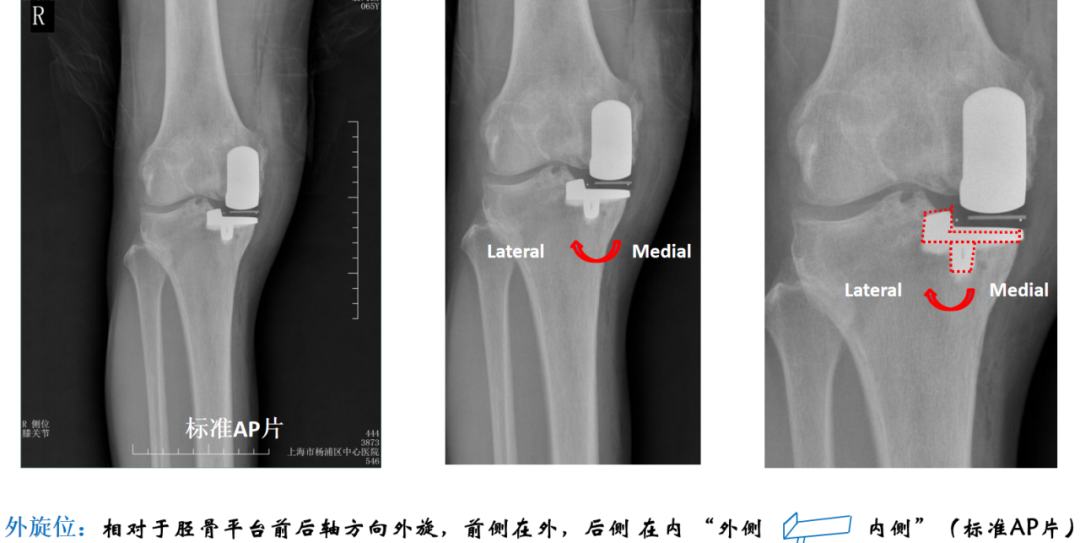

胫骨假体中立位(横断面:无内外旋)

胫骨假体内旋

胫骨假体外旋